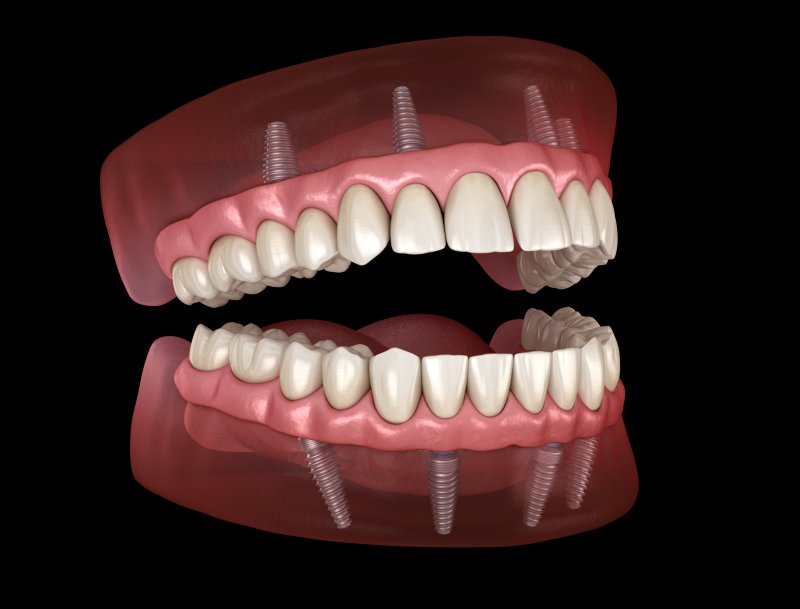

Back in the day, if you were missing teeth, your only real option would be dentures. However, with modern dental technology, there are various solutions out there that can give you your smile back. Dentures are an excellent option for many people, but implant dentures are becoming more popular thanks to their incredible benefits. Continue reading to learn more about implant dentures and how they can help you get your smile back!